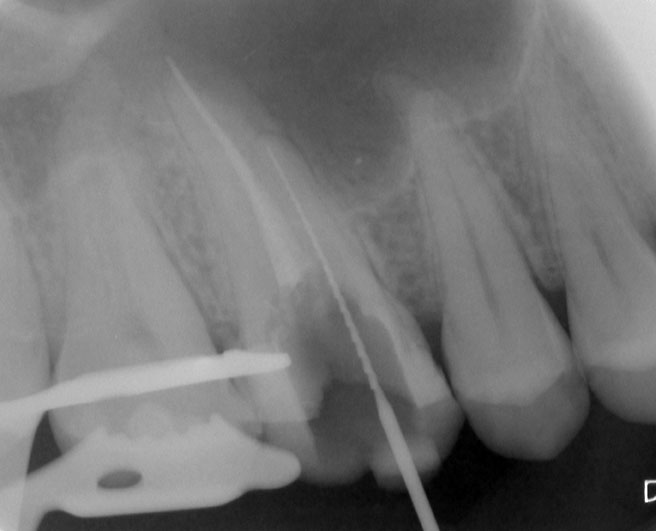

Nach erfolgter Information über die vermutete Prognose unternehmen wir den Versuch, das frakturierte Instrument darzustellen. Nach Entfernung der Aufbaufüllung werden die Kanaleingänge dargestellt (Abb. 2). Es zeigt sich, dass neben dem distovestibulären Kanal auch ein vierter Kanal (mb2) vorhanden ist. Die Darstellung der Wurzelkanaleingänge erfolgt in unserem Haus mit dem Aufsatz 1R des Tigon+. Dank der Abwinkelung des Instruments profitiert man von einer sehr guten Sicht auf die Behandlungsstelle. Zudem erlaubt es ein schnelles und gezieltes Abtragen von Dentin, ohne dabei den Zahn unnötig zu schwächen.

Nach Darstellung aller Wurzelkanaleingänge wird in einem zweiten Schritt das frakturierte Wurzelkanalinstrument dargestellt (Abb. 3 u. 4). Hierfür verwenden wir den Aufsatz 3E des Tigon+. Durch die schmale und lange Form des Instruments erreichen wir einen tiefen und schmalen Zugang.